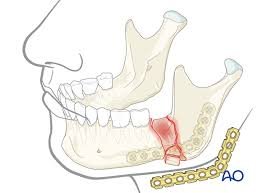

Jaw Fracture Treatment

Specialized care for jaw fractures and trauma. Our advanced treatment techniques ensure proper healing and restoration of jaw function.

Expert Jaw Fracture Treatment in Ghaziabad — Dental Esthetix

A jaw fracture isn’t just painful—it can be life-altering if not treated properly. From difficul...